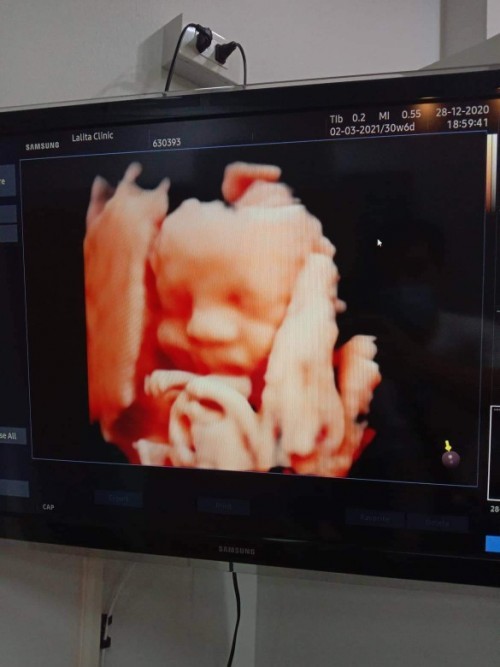

ผู้หญิงค่ะ กำหนด 2/3/64 แต่คาดว่าน่าจะแตกก่อน🥰🥰